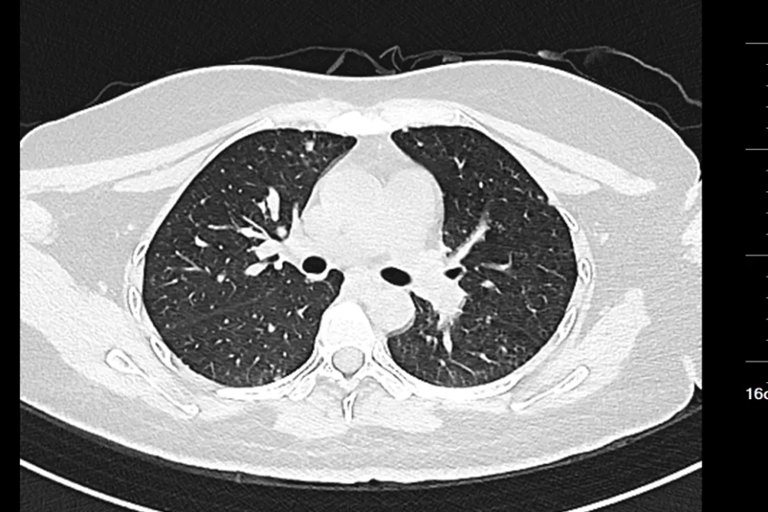

Hình ảnh chụp CT của nữ sinh 20 tuổi

Gần đây, một phụ nữ ngoài 20 tuổi đến khám tại Bệnh viện Nhân dân Đông Hoản (Quảng Đông, Trung Quốc) vì phát hiện khối u ở cổ trái trong khoảng một tuần.

Trước đó, cô cảm thấy vùng cổ đau nhẹ và sờ thấy một khối cứng kích thước gần bằng quả trứng gà. Khối u ấn vào có cảm giác đau nhưng không đỏ, không sưng. Điều đáng nói là cô không hề có triệu chứng tiêu hóa rõ ràng như đau bụng, đầy hơi hay sốt, ăn uống và đại tiện vẫn bình thường.

Sau khi nhập viện để kiểm tra toàn diện, bác sĩ tiến hành nội soi dạ dày và sinh thiết hạch cổ. Kết quả giải phẫu bệnh cho thấy bệnh nhân mắc ung thư biểu mô tuyến kém biệt hóa, trong đó có thành phần ung thư tế bào nhẫn - một dạng ung thư dạ dày ác tính cao.

Chụp CT cho thấy khối u đã di căn toàn thân, không còn chỉ định phẫu thuật. Các bác sĩ chỉ có thể đề nghị điều trị bằng hóa trị, xạ trị hoặc liệu pháp miễn dịch nhằm kiểm soát bệnh.